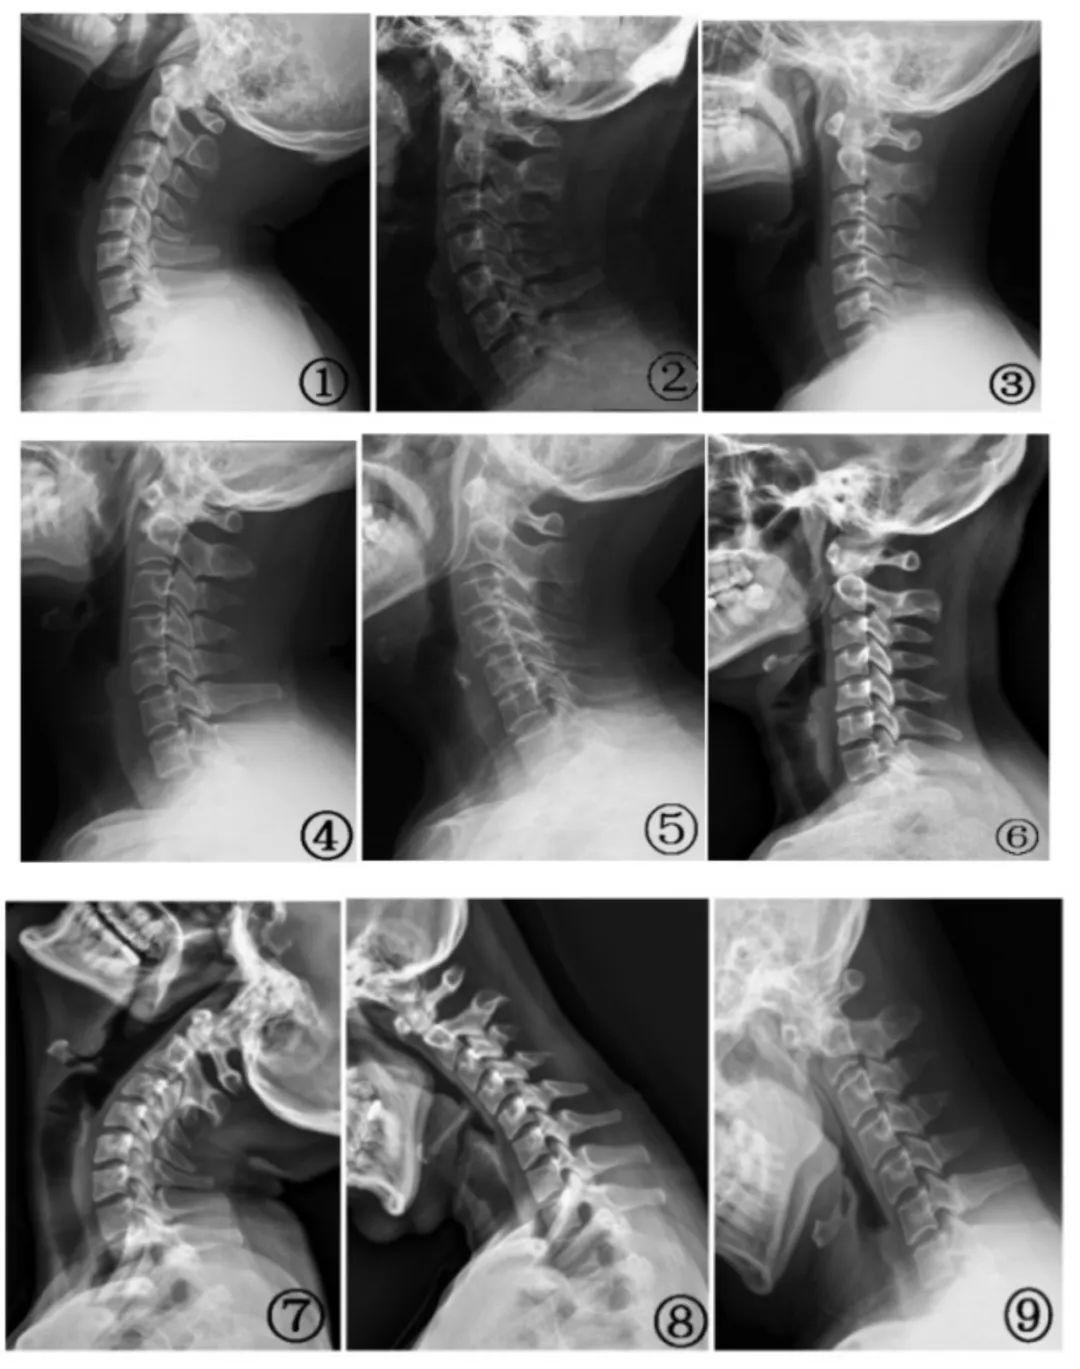

正常情况下,人类的脊柱存在 4 个生理曲度,包括颈胸腰骶四个曲度,其中颈椎会呈现出一个“C”形的自然生理曲度,四个生理弯曲上下延续,就好像一条波浪线,其中一个曲度变化,会连带着上下曲度一起发生变。

颈椎生理曲度变直是现代人常见的健康问题,其诱发因素较多,包括职业因素、疾病因素、生活习惯因素等。

疾病因素主要有三个方面,一是慢性退行性病变,例如中老年人因椎间盘脱水、弹性下降,椎间隙变窄,自然退变导致曲度消失,甚至可引起颈椎病、后纵韧带、黄韧带骨化等疾病,严重时还可能导致肌力下降甚至瘫痪;二是颈椎间盘突出、强直性脊柱炎、结核或肿瘤等也会直接改变颈椎结构;三是外伤,颈部撞击、扭伤等急性损伤也可加速颈椎曲度变化。

如果颈椎生理曲度变直,会对关节周围的骨头、肌肉以及韧带等产生不良影响,引发临床症状。

1.单纯颈椎曲度变直可能没有临床症状,或是偶发颈部僵硬、胀痛等,经过休息或按摩可以缓解。

2.长时间颈椎曲度,外形上可引起头前伸、富贵包、驼背、圆肩、脖子缩短粗、双下巴、脸型不对称等。

3.严重的颈椎曲度变直则可因伴发颈椎病、神经根受压等疾病而出现手部麻木、颈部疼痛不适等,更严重的时候会出现头晕、眼花、恶心、走路眩晕等症状,还可能导致肌力下降甚至瘫痪。